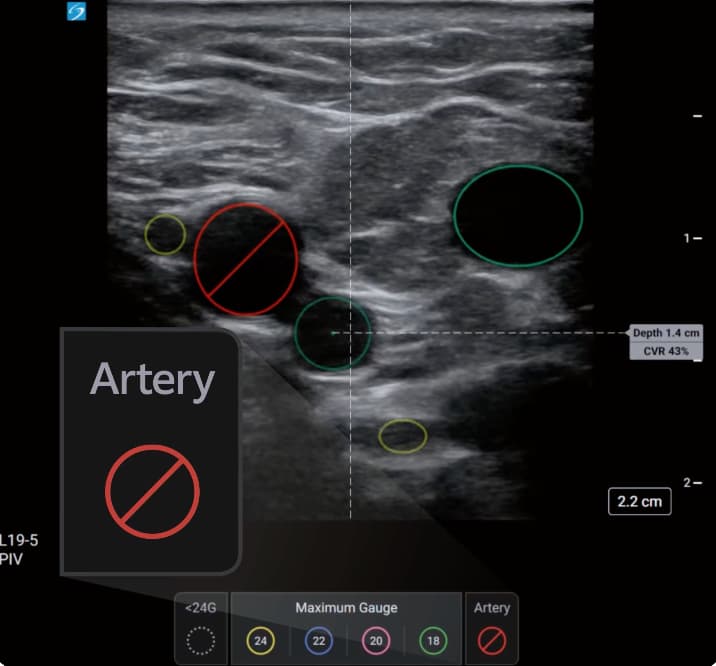

The AI-driven tool aims to assist healthcare professionals by identifying candidate veins and assessing vessel size during pre-procedural scanning. PIV Assist provides real-time differentiation between veins and arteries whilst calculating the catheter-to-vein ratio (CVR) to recommend maximum cannula sizes.

The system employs colour-coded visual guidance to assist procedural planning. Veins are marked according to maximum recommended catheter gauge, whilst arteries appear highlighted in red. The feature displays CVR calculations in real-time and indicates the depth to the centre of each identified vessel.